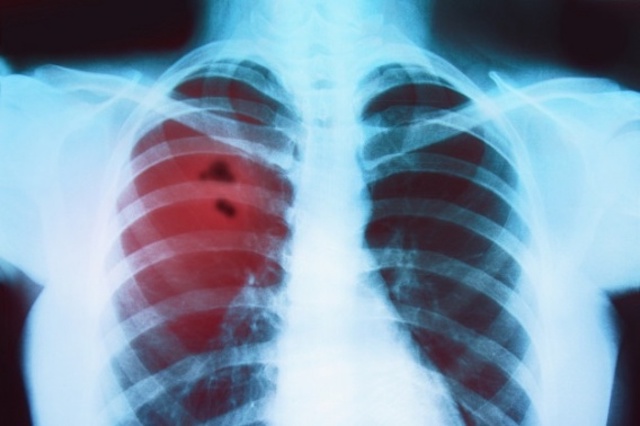

Из-за роста заболеваемости коронавирусом в Николаеве, меняются места госпитализации пациентов с пневмонией

«Сегодня такое количество заболевших ковидом, что невозможно сконцентрировать всех пациентов с пневмонией на базе одного лечебного заведения. Поэтому, если у больного нет подтвержденного коронавируса, но есть пневмония, его госпитализируют по месту жительства. Если же covid таки диагностируют, то человека переведут в коронавирусный госпиталь на базе городской больницы №1», - сообщила начальница управления охраны здоровья Николаевского горсовета Ирина Шамрай.

Отметим, что по сегодня, 6 сентября, в Николаеве 55 новых случаев коронавируса. В 1-й горбольнице находятся 137 пациентов с подтвержденным covid. Заполненность коек – 46,7 процента.